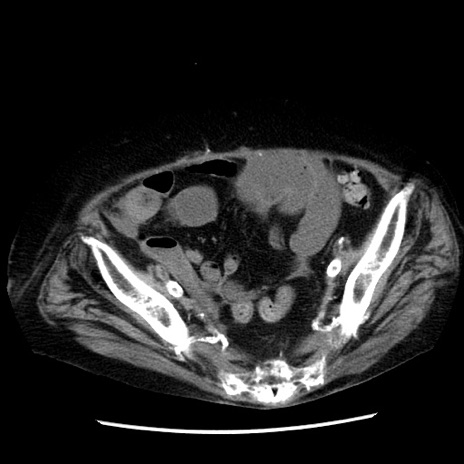

症例14(横断像)

【症例】 90歳代女性

【主訴】 腹痛・嘔吐

【現病歴】今朝から左側腹部痛を認めた。 経過観察していたが、嘔吐を認めたため来院。

【既往歴】 子宮癌術後

【身体所見】 意識清明、BP 127/54mmHg、P 98bpm Sp02 95%(RA)、BT 35.8°C、腹部平坦・軟腸ぜん動音聴取良好、右下腹部圧痛(+) 反跳痛なし

【データ】WBC 9800、CRP 0.46